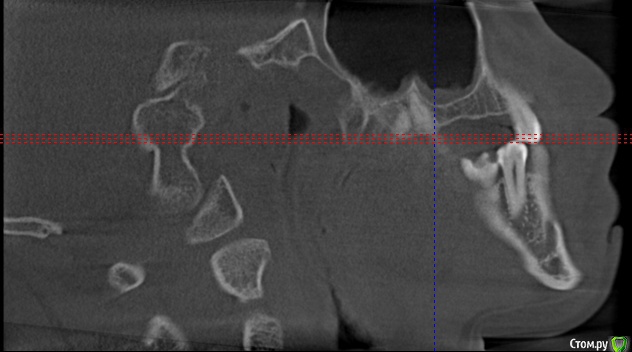

Секатор Опубликовано 4 октября, 2015 Поделиться Опубликовано 4 октября, 2015 (изменено) Здраствуйте,уже писал,но проблем много,но сча есть снимки зд(ссори за флуд).Начну издалека года два летом примерно неделю начили болеть зубы справа с отдованием в ухо и висок,оперативно ничего не делал(спас ал алкоголь),но я решил,что это 8-ки,и за зиму последнию все удалил,но отдования в висок и болезненность уха осталось,много времени прошло после удаления.Напряжение у виска и в области уха,взгляните на мою 6 справа,дно пазухи деформировано под её давлением,боли в области зуба нет-она причина?По лор все чисто,как будто болит зуб отдовая в ухо и висок,но без боли в области челюсти.Ближе к внутренней стенки пазухи и заходя на неё сформирован остроконечный конус дном пазухи,вследствии давлении корня зуба. Изменено 4 октября, 2015 пользователем Секатор 1 Ссылка на комментарий

Секатор Опубликовано 15 октября, 2015 Автор Поделиться Опубликовано 15 октября, 2015 Здравствуйте,сос...Рано поспешил радоваться,дело в следующем мне хорошо обкололи,и сверлили 47,положили мышьяк,ухо прошло на два часа,как в сказке был,но боль снова началась.Невралгия нерва по-любому есть,а вот причина!И,что где-то рядом с зубами.Все-таки планирую удалять 7 справа сверху,а ккак быть?Придётся методом тыка,у 7 корня небольшое утолщение слизистой пазухи,но вот ещё что,на уровне 5,6 была киста пазухи,прошла после удаления зубов. Ссылка на комментарий

Секатор Опубликовано 15 октября, 2015 Автор Поделиться Опубликовано 15 октября, 2015 (изменено) И,ещё раз прошу взглянуть смотрите,как деформирована внутреннеяя стенка пазухи зубом,у дна.Может корень подцепил,стенку пазухи? Изменено 15 октября, 2015 пользователем Секатор Ссылка на комментарий

Секатор Опубликовано 15 октября, 2015 Автор Поделиться Опубликовано 15 октября, 2015 Блин,все попутал разговор сначала про 7 сверху,на первых снимках 8 и7. Ссылка на комментарий